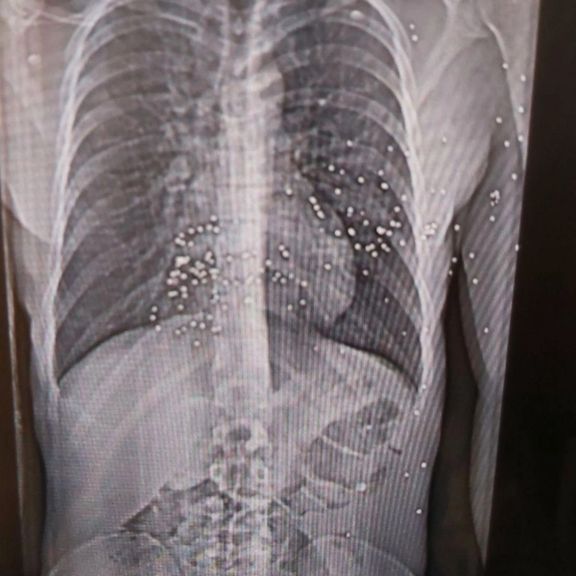

مجله نیویورکر گزارش داد جمهوری اسلامی میکوشد کشتار اخیر در جریان انقلاب ملی را به «فراموشی اجباری» بسپارد و در این مسیر، علاوه بر معترضان مجروح، کادر درمان را نیز تحت فشار قرار داده است. افرادی که شاهد جنایتهای هولناکی بودهاند.

نیویورکر نوشت اعضای کادر درمان در هفتههای اخیر خود به مستندسازی شواهد حملات حکومت به مردم ایران پرداختهاند و برخی مدارک از جمله تصاویر سیتیاسکن مجروحان را در اختیار این مجله قرار دادهاند.

نرگس این وضعیت را «جهنمی» توصیف کرد: نوجوانی ۱۴ ساله با پاهایی نحیف که با ساچمههای فلزی هدف قرار گرفته بود؛ مردی با حفرهای به اندازه توپ تنیس در ساق پا که او در بخیه زدن آن کمک کرد.